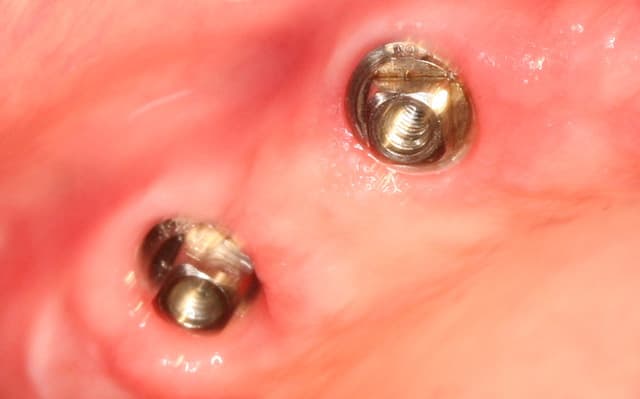

Cas clinique n° 3

posit, le cas 3, avec les deux implants symphysaire, sans doute pour locator, a quand même l'air assez simple a main-levé .

J’en ais eu plusieurs pour 2 et 4 implants symphysaire, outre le fait de paralléliser ou avoir une angulation maitrisée la procédure permet un lambeau à minima et une localisation de l’artère sublinguale. Cette intervention peut être parfaitement réalisée à main levée. Lorsqu’ ‘il y a défaut de parallélisme des usures prématurées des Locator peuvent être constatées. Une chirurgie à main levée à un coût plus économique qu’une chirurgie guidée le choix peut se faire aussi en thermes de sécurité, confort, résultat,…